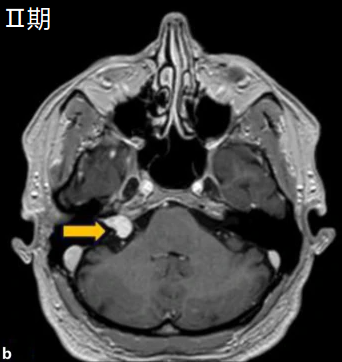

• Ⅱ期:腦池期

小型腫瘤,腫瘤直徑為1-14mm,腫瘤進(jìn)入橋小腦角區(qū),但是未接觸腦干,主要癥狀為聽神經(jīng)受損癥狀。

Ⅱ期:腦池期